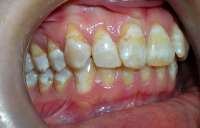

Аноним 19/02/17 Вск 21:50:52  574925

image.jpg (162Кб, 577x374)

image.jpg (368Кб, 828x687)

image.jpg (92Кб, 427x309)

image.jpg (153Кб, 420x495)

Сап. 21 лвл тянТакая проблема. С детства у меня какая-то херня с уздечкой, большая очень, говорили, что надо подрезать. Но делать этого нельзя, пока все зубы не вырастут. Несмотря на все, были изначально кривыми, но в итоге неплохим прямым рядом стоят. Знаю, что есть проблемы с нижним рядом, но стоматолог сказал, что небольшие, брекеты буду ставить в любом случае из-за прикуса. Так вот вопрос, собственно, в том, можно ли сейчас и как резать уздечку. У нас ортодонты в районной очень плохие, даже мой стоматолог сказала я хожу к детскому стоматологу с районной платно, но она очень крутой специалист. Еще осложняется все тем, что зубы лезут неохотно. Последний молочный зуб вырвали только в 11 классе, когда начинал расти новый правый верхний клык. Соседняя четверка, несмотря на то, что была удалена задолго до этого, вообще только в универе выросла и то не до концасказали, потому что зубы большие. Восьмерок нет пока даже в зачатках. Можно ли делать пластику уздечки сейчас, уберет ли это щель между резцами, или забить хуй?

Фотки с плохим качеством, извиняюсь, но меня интересует не кариес, а именно уздечка.

>>574925

Кариес лучше полечи 4.4

>Можно ли делать пластику уздечки сейчас

её давно можно было делать. Я даже не понимают чем руководствовались , когда говорили "жди пока все прорежутся" хотя мб я неуч. лол. Я б ебанул её. И себе надо бы ебануть, хоть щели у меня нет.

Щель у тебя никуда не денется, если сделаешь пластику.Но и ухудшения ситуации также не будет происходить. Так что делай.

>>574968

Только из твоего поста понял, что это тян.

Ну я смотрю на щели. Сегодня ебся с пациенткой, которой менял пломбу на передних зубах. Были залепухи ну и зубы стоят не ровно. В итоге получилась "щель". Ну хуле делать. Заебала меня малеха, но подзамазал это добро и чуть добавил, чтобы казалось, что он ровней стоит чем есть. Была довольна.

Так что... Пусть фиксит. Ну а по первому пику то могу сказать, что в принципе тут можно сделать косметическую реставрацию тупо композитом. ПОсмотреть че как и как долго стоять будет. А дальше думать - или в будущем опять закрыть щель композитом, если наебнется по какой-то причине. Либо виниры ебануть

>>574995

Только что лечила зубы, идеально все, нигде кариеса не осталось. Это налет, чистку позже сделаю

>>575007

Ок, тогда отхуячу к черту уздечку